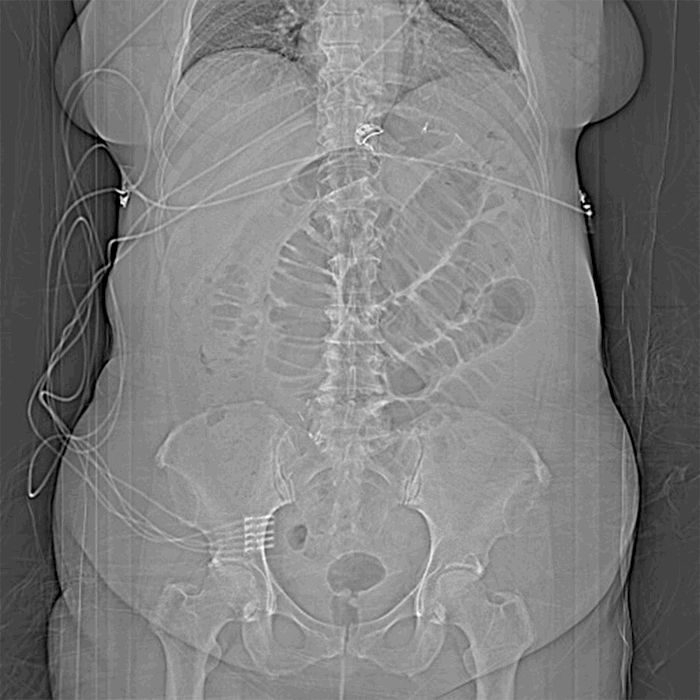

The differential diagnosis consisted of an internal hernia causing a small bowel obstruction in a gastric bypass patient, followed by adhesions due to previous surgery, peptic ulcer disease, and a recurrence of a hiatal hernia. The patient was taken to the OR for diagnostic laparoscopy reduction of distal small bowel obstruction; the abdomen was prepped and draped in a usual sterile fashion; a trocar was placed in left upper quadrant and pneumoperitoneum was established; laparoscopic trocar ports were placed for this procedure. Upon this, we found dilation of the gastric remnant from the mid-jejunum biliopancreatic limb and small bowel distal to the jejunojejunostomy. At this point, distal jejunum was found to have a band between the jejunojejunostomy and what appeared to be a Meckel diverticulum (Figure 3 and Figure 4).

Figure 3. Meckel diverticulum with adhesive band taken down.

The band was lysed with a Harmonic scalpel. Running the remainder of the jejunum to the terminal ileum showed a Meckel diverticulum, which was resected with a stapling device without difficulty and removed.